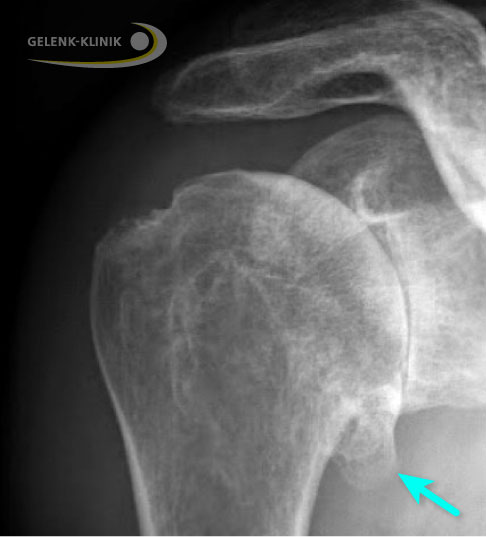

Bildgebung: Röntgen, MRT und CT bei Omarthrose

Zur Sicherung der Diagnose röntgt der Schulterspezialist die betroffenen Schulter und führt bei unklarem Zustand der Sehnen der Rotatorenmanschette eine Kernspintomographie (MRT) durch.

Bestehen Knochendefekte, wie sie bei einem langen Verlauf der Schulterarthrose vor allem im hinteren Bereich der Pfanne (Glenoid) auftreten können, ergänzt der Schulterspezialist die Diagnostik durch eine Computertomographie (CT). Die CT-Technik ermöglicht dem Arzt bei große Knochendefekten eine 3-D-Planung zur optimalen Vorbereitung, wenn er eine Operation in Betracht zieht.

Wichtige Fragen ans Röntgen:

- Gibt es Knochensporne (Osteophyten) am Gelenkrand?

- Ist der Gelenkspalt schmaler geworden?

- Gibt es Hohlräume (Zysten) im Knochen des Oberarmkopfes?

- Sind Verkalkungen in den Weichteilen sichtbar?

- Ist der Oberarmkopf verformt?

- Ist der Oberarmkopf nach hinten verschoben (Subluxation)?

Auf Röntgenaufnahmen erkennt der Schulterspezialist die typische Verschmälerung des Gelenkspalts bei Omarthrose. Die primäre Schulterarthrose zeigt in vielen Fällen eine Knorpelabnutzung der hinteren Anteile der Gelenkpfanne. Osteophyten sind Zeichen einer fortgeschrittenen Arthrose. Im späten Krankheitsstadium kann der Oberarmkopf ebenfalls verformt (deformiert) sein.